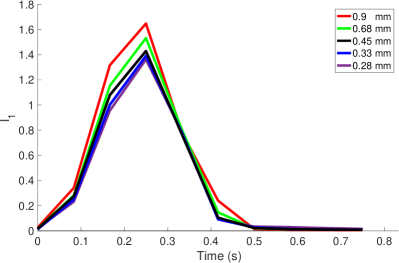

We performed a convergence study to evaluate the sensitivity of the phase-averaged velocity fields and flow rates to changes in simulation resolution. The fluid resolutions were set to 0.9, 0.68, 0.45, 0.34 and 0.28 mm. We ran each simulation ran for two cardiac cycles, then performed phase averaging on the second cycle and sampled onto the MRI mesh for comparisons, as described in Section 3.4. For 0.9 and 0.68 mm, we used a coarsened structure mesh with a target edge length of mm, for 0.45 and 0.34 mm we used the target edge length of mm, as used in the remainder of this work, and for 0.28 mm we use the leaflet mesh targeted to mm, and a slightly finer mesh for the vessel targeted to mm.

The flow rates, depicted in Figure 12, increase with increasing resolution, also as expected given the increase in effective valve orifice area and radius. The maximum flow rates at 0.45 and 0.34 mm were 248.6 and 281.4 ml/s, respectively, a relative difference of 11.7%. The mean flow rates at 0.45 and 0.34 were 55.5 and 63.2 ml/s, respectively, a relative difference of 12.4%. The maximum flow rates at 0.34 and 0.28 mm were 281.3 and 299.8 ml/s, respectively, a relative difference of 6.1%. The mean flow rates at 0.34 and 0.28 mm were 63.2 and 67.4 ml/s, respectively, a relative difference of 6.2%. Thus the flow rates show signs of converging with increasing resolution, though some minor differences remain.

Figure 13 shows the integral metric evaluated at cm with various resolutions, where each resolution uses its own velocity scale (see eqn. (18)). Values at 0.9, 0.68 were elevated relative to finer resolutions, indicating under resolution. Values of at 0.45, 0.34 and 0.28 mm are extremely similar, with slight decrease as resolution increases. Values of at 0.625 and 1.25 cm showed similar trends and are not shown.

Given the overall qualitative similarity and relative changes in flow rates, we believed all conclusions in this work would be similar with 0.45, 0.34 or 0.28 mm. We therefore selected 0.45 mm, twice the MRI resolution, for the main portion of this study.